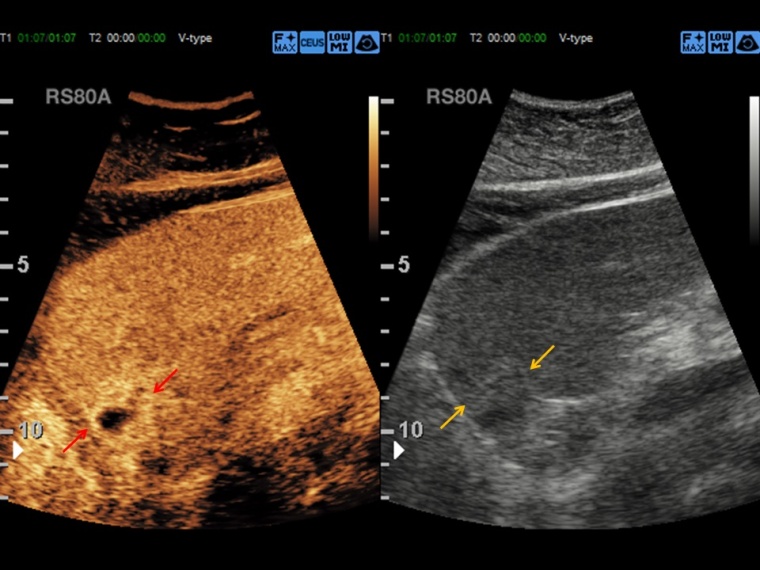

Der kontrastmittelverstärkte Ultraschall, CEUS (Contrast Enhanced Ultrasound) nutzt gasgefüllte Mikrobläschen als Kontrastverstärker zur Erstellung des Sonographiebildes.

Prof. Dr. Dirk-André Clevert: CEUS eignet sich hervorragend für die Beurteilung der Makro- und Mikrozirkulation von Organsystemen, die grundsätzlich für sonografische Fragestellungen untersuchbar sind. Dies umfasst diagnostische Fragestellungen im Bereich der Beurteilung von Läsionen und Raumforderungen von parenchymatösen Oberbauchorganen, aber auch die vaskuläre Diagnostik von Gefäßen, z. B. bei Patienten nach endovaskulärer Aortenreparatur. Ein Großteil der Diagnostik in unserer Abteilung behandelt die Abklärung von unklaren Leberraumforderungen oder komplexer Nierenzysten.

Clevert: CEUS ist eine schnelle, leicht durchzuführende und kosteneffektive Methode zur Diagnostik von abklärungsbedürftigen Befunden. Der Vorteil der Methode liegt in der schnellen Verfügbarkeit und der Dynamik der Untersuchungsmethode. Können in alternativen radiologischen Schnittbildgebungen beispielsweise nur einzelne Kontrastphasen akquiriert werden, so ist es mit dem CEUS möglich, die dynamische Perfusion von Gewebe oder von Gefäßen über mehrere Minuten zu beobachten, und so differenzierte Aussagen zu treffen. Ein weiterer großer Vorteil der Methode besteht darin, dass das verwendete Kontrastmittel unabhängig von der Nieren- und Schilddrüsenfunktion verwendet werden kann und somit der CEUS auch bei Patienten mit Niereninsuffizienz bzw. mit hyperthyreoter Stoffwechsellage zum Einsatz kommen kann.

Clevert: Neben der reinen Diagnostik wird in Zukunft ein immer größerer Anteil der Methode auch in der Evaluation des Therapiemonitoring bzw. -ansprechens liegen. Vielversprechende Ansätze gibt es auch in der Entwicklung neuer Kontrastmittel, die spezifisch für eine bestimmte Krankheit verwendet werden können, wie beispielsweise zur Detektion des Prostatakarzinoms.